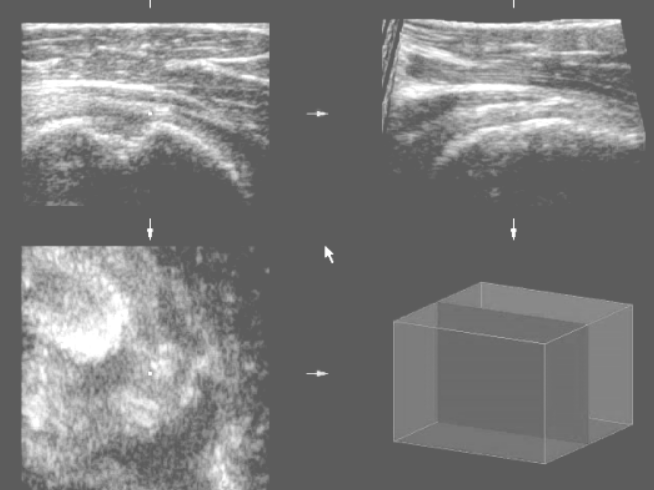

Obr.2

Humerus head – calcified tendinitis of rotator cuff -manually mede (by electronic pen) contour of bony structures in multiplanar cuts and automatically generated model of bony structures

Ob.r 2

Hlavice humeru s ektopickou kalcifikací v manžetě rotátorů. Po manuálním vyznačení elektronickým perem v multiplanárním zobrazení je automaticky vygenerován prostorový model